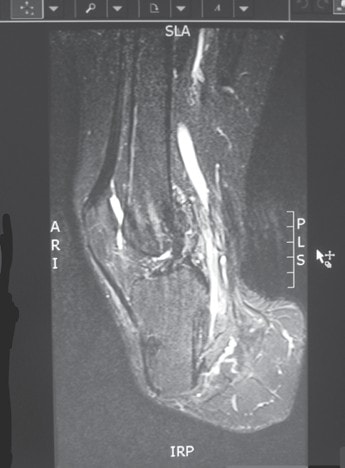

Um nicht zu viel Spannung auf die Muskulatur auszuüben, bedarf es des Vorstellungsvermögens des Operateurs über die natürliche Vorspannung, da intraoperativ kein Messgerät zum Messen der Vorspannung zur Verfügung steht. Dies ist durchaus ein Problem. Es bedarf dazu einiger operativer Erfahrung, was zur Folge hat, dass eine Amputation keine Anfängeroperation sein kann. Die unter physiologischer Vorspannung stehende Muskulatur wird mit dünnen Fäden der Stärke 00 am Periost bzw. Muskel zu Muskel befestigt. Dabei bleiben auch bei sorgfältiger Nahttechnik zumindest kleine Zwischenräume, die zwar mit zwei Drainagen behandelt werden, aber trotzdem etwas Hämatom oder Serom beinhalten. Das bedeutet bei der großen Wundfläche einige Quadratzentimeter, die einer längeren Heilungszeit (Konsolidierungszeit) nach Abschluss der oberflächlichen Narbenbildung bedürfen. Müller-Wohlfahrt et al. 8 haben ihre Erfolge bezüglich der relativ schnellen Muskelheilung nach Muskelfaserriss, Muskelbündelriss und totaler Muskelruptur anlässlich der 64. Jahrestagung der VSOU im Jahr 2016 so erklärt, dass das im Bereich des Risses vorhandene Hämatom/Serom punktiert werde und sich so die Rissenden wieder annähern und somit schneller verheilen könnten (Abb. 7, 8, 9a u. b).

Eine Heilung mit Hämatom/Serom benötigt demzufolge eine längere Zeit (Konsolidierungszeit). Solange diese nicht vollständig abgeschlossen ist, ist der Stumpf bei unnötiger Belastung durch das Abreißen der Muskulatur gefährdet (Abb. 6a). Müller-Wohlfahrt et al. geben folgende Heilungszeiten bei Sportlern an: